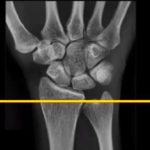

Image Quiz 10 #Wrist

What are your treatment options? Use the Poll and write your answers in the Comments section below. Popular Answer may not imply right answer. Follow our twitter handle for the right answer, https://twitter.com/drhiteshg/status/567308751305076736?s=01